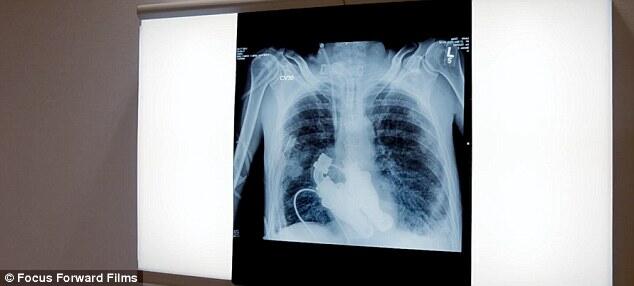

Pada bulan Maret tahun lalu, Craig Lewis, 55, dalam kondisi sekarat karena kondisi jantung yang menyebabkan pembentukan protein abnormal, dengan kondisi ini bahkan alat pacu jantung tak dapat membantu menyelamatkan hidupnya. Craig Lewis (55), adalah orang pertama yang menggunakan pompa 'aliran kontinu' untuk menggantikan fungsi jantung Tapi dua dokter dari Texas Heart Institute mengusulkan solusi baru yang revolusioner, yakni menginstal perangkat yang akan memungkinkan darah bersirkulasi dalam tubuhnya tanpa denyut jantung.

Dr Billy Cohn dan Dr Bud Frazier kemudian menginstal perangkat tersebut setelah mengeluarkan jantung Lewis. Dan dalam waktu beberapa hari, sang pasien sudah bangun dan berbicara dengan dokter.

Perangkat tersebut bekerja dengan memasok aliran darah secara kontinu melalui tubuh, dengan menggunakan baling-baling.